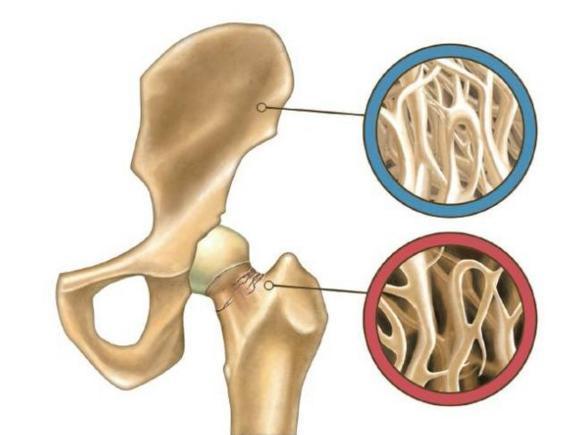

5.骨傷康復(fù):各種骨關(guān)節(jié)炎,肌肉拉傷、挫傷,髖膝關(guān)節(jié)置換等骨科術(shù)后運(yùn)動功能恢復(fù)。